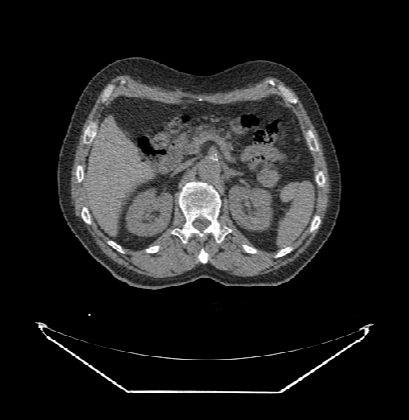

DcmViewer是一个纯客户端的即时医疗影像系统,支持标准的DICOM影像文件,用来提供看图阅片等功能,同时支持一些配套图形操作工具,使用过程中不会保存任何影像信息到服务器端。在进入系统后,系统将自动从服务器上下载一个样例数据,因为一套完整的CT数据大约有几十兆大小,下载完整的数据,需要一定的时间,为了提高样例的加载效率,DcmViewer首先下载其中的10张样例数据,显示为2D图像。

如果需要浏览样例的3D图像,点击工具箱里的“三维”按钮,等样例数据全部图片加载完成后即可查看。

3D图像界面:

同时,DcmViewer支持移动端,当屏幕不足够大时,只显示最基本的视图布局切换和影像图片导航功能(样例数据将不支持冠状面和矢状面)。